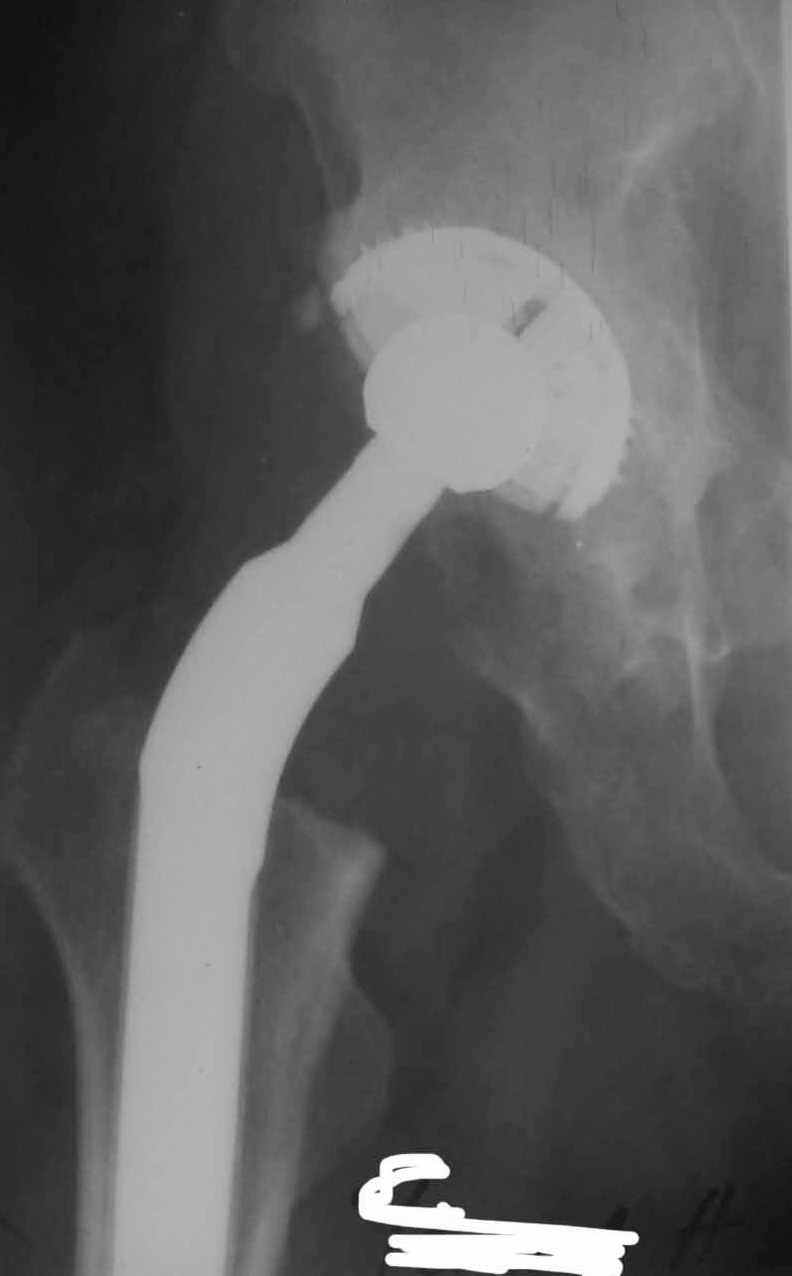

Во вложении - рентгенограммы после вывиха и после вправления.

1. AP X ray of the Pelvis is a must. It will likely show that right hip/ femur is longer than left. Even based on Rt Hip AP X Ray it is my impression.

2. 2. Acetabular component is not vertical but rather anteverted, and also small ( small size was likely used because of the deficient posterior wall of the acetabulum).

3. Femoral component is malaligned relatively to the acetabular and combination of this factors (head is also small for this patient) is the reason for dislocation.( was likely anterior)